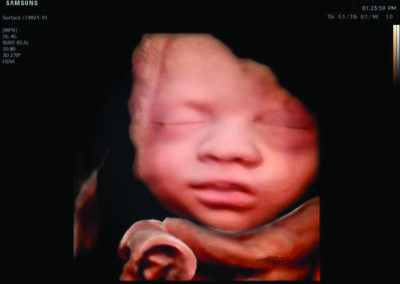

Comprehensive, advanced and expert MFM care for high-risk pregnancies

- Fetal anomalies